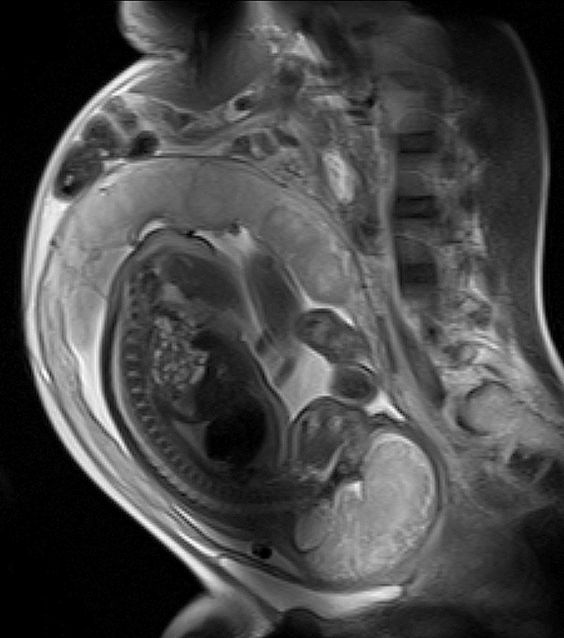

МРТ плода при беременности проводится для подтверждения данных УЗ-скрининга при следующих состояниях:

- Аномалии нервной трубки (гидроцефалия, грыжа головного мозга, киста оболочек головного мозга, анэнцефалия и др.)

- Аномалии грудной клетки (грыжа диафрагмы, секвестрация или гипоплазия легких).

- Аномалии брюшной полости (грыжа пупочного канатика(омфалоцеле), лимфангиома, и др.)

- Аномалии мочевыделительного тракта (неразвивающиеся почки, поликистоз почек).

- Аномалии костно-суставного аппарата (несовершенный остеогенез).

- Опухоли (тератома, лимфангиома).

- Обнаружение сиамских близнецов.

- Сочетанные пороки.